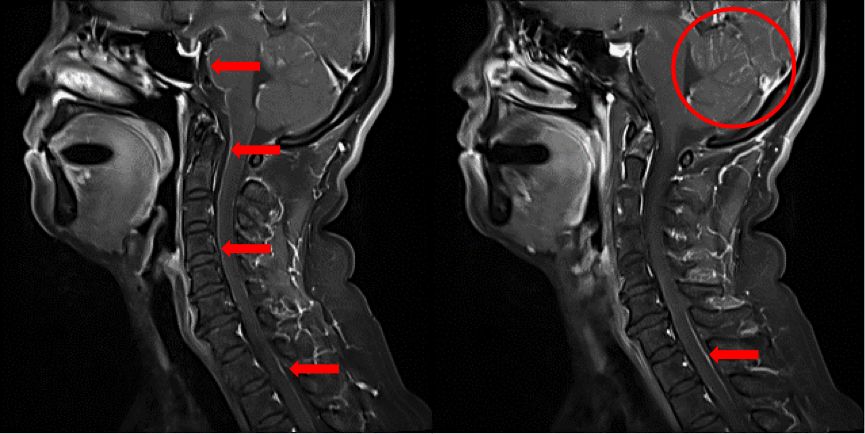

近日,郑州大学附属第一医院肿瘤科李醒亚教授团队分享了一例ALK+脑膜转移肺腺癌患者诊疗的临床常见经典病例,并对临床脑膜转移的诊断和治疗提出了自己的思考。该患者为49岁、非吸烟、女性患者,因“干咳1月”于2018年1月就诊于上海交通大学附属胸科医院,PET/CT检查提示左肺近肺门处软组织肿块影伴局部代谢活跃,大小约45mm*18mm,SUVmax7.2,双肺弥漫结节影,代谢增高,双肺转移可能性大,左侧胸腔可见少量胸腔积液;2L、4L、7组淋巴结肿大,最大淋巴结位于4L组,大小约22*16mm,SUVmax 4.9;骶骨骨质破坏伴局部代谢活跃。头颅增强MRI检查未见明显转移征象。诊断考虑左肺中央型肺癌伴单发骶骨转移可能。

图1.患者全身PET/CT影像